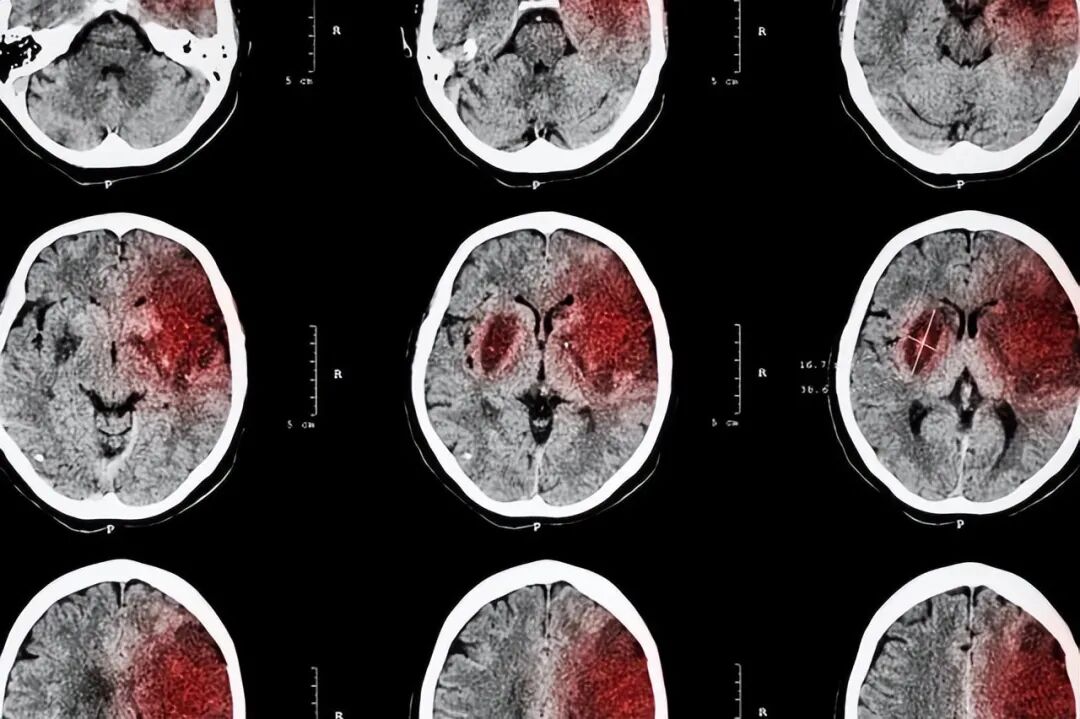

缺血性脑血管疾病,是指由于供血障碍,局部脑组织变性、坏死,导致持续性或一过性神经功能缺失,是神经系统常见疾病之一,好发于中老年人群,其发病率、致残率、病死率、复发率均较高。包括:短暂性脑缺血发作和急性缺血性脑卒中。